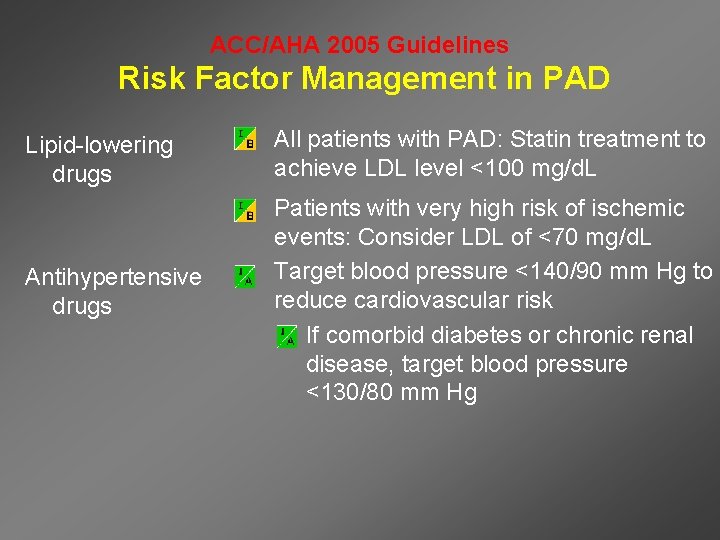

ACC/AHA 2005 Guidelines Risk Factor Management in PAD Lipid-lowering drugs • All patients with PAD: Statin treatment to achieve LDL level <100 mg/d. L Antihypertensive drugs • Patients with very high risk of ischemic events: Consider LDL of <70 mg/d. L • Target blood pressure <140/90 mm Hg to reduce cardiovascular risk – If comorbid diabetes or chronic renal disease, target blood pressure <130/80 mm Hg